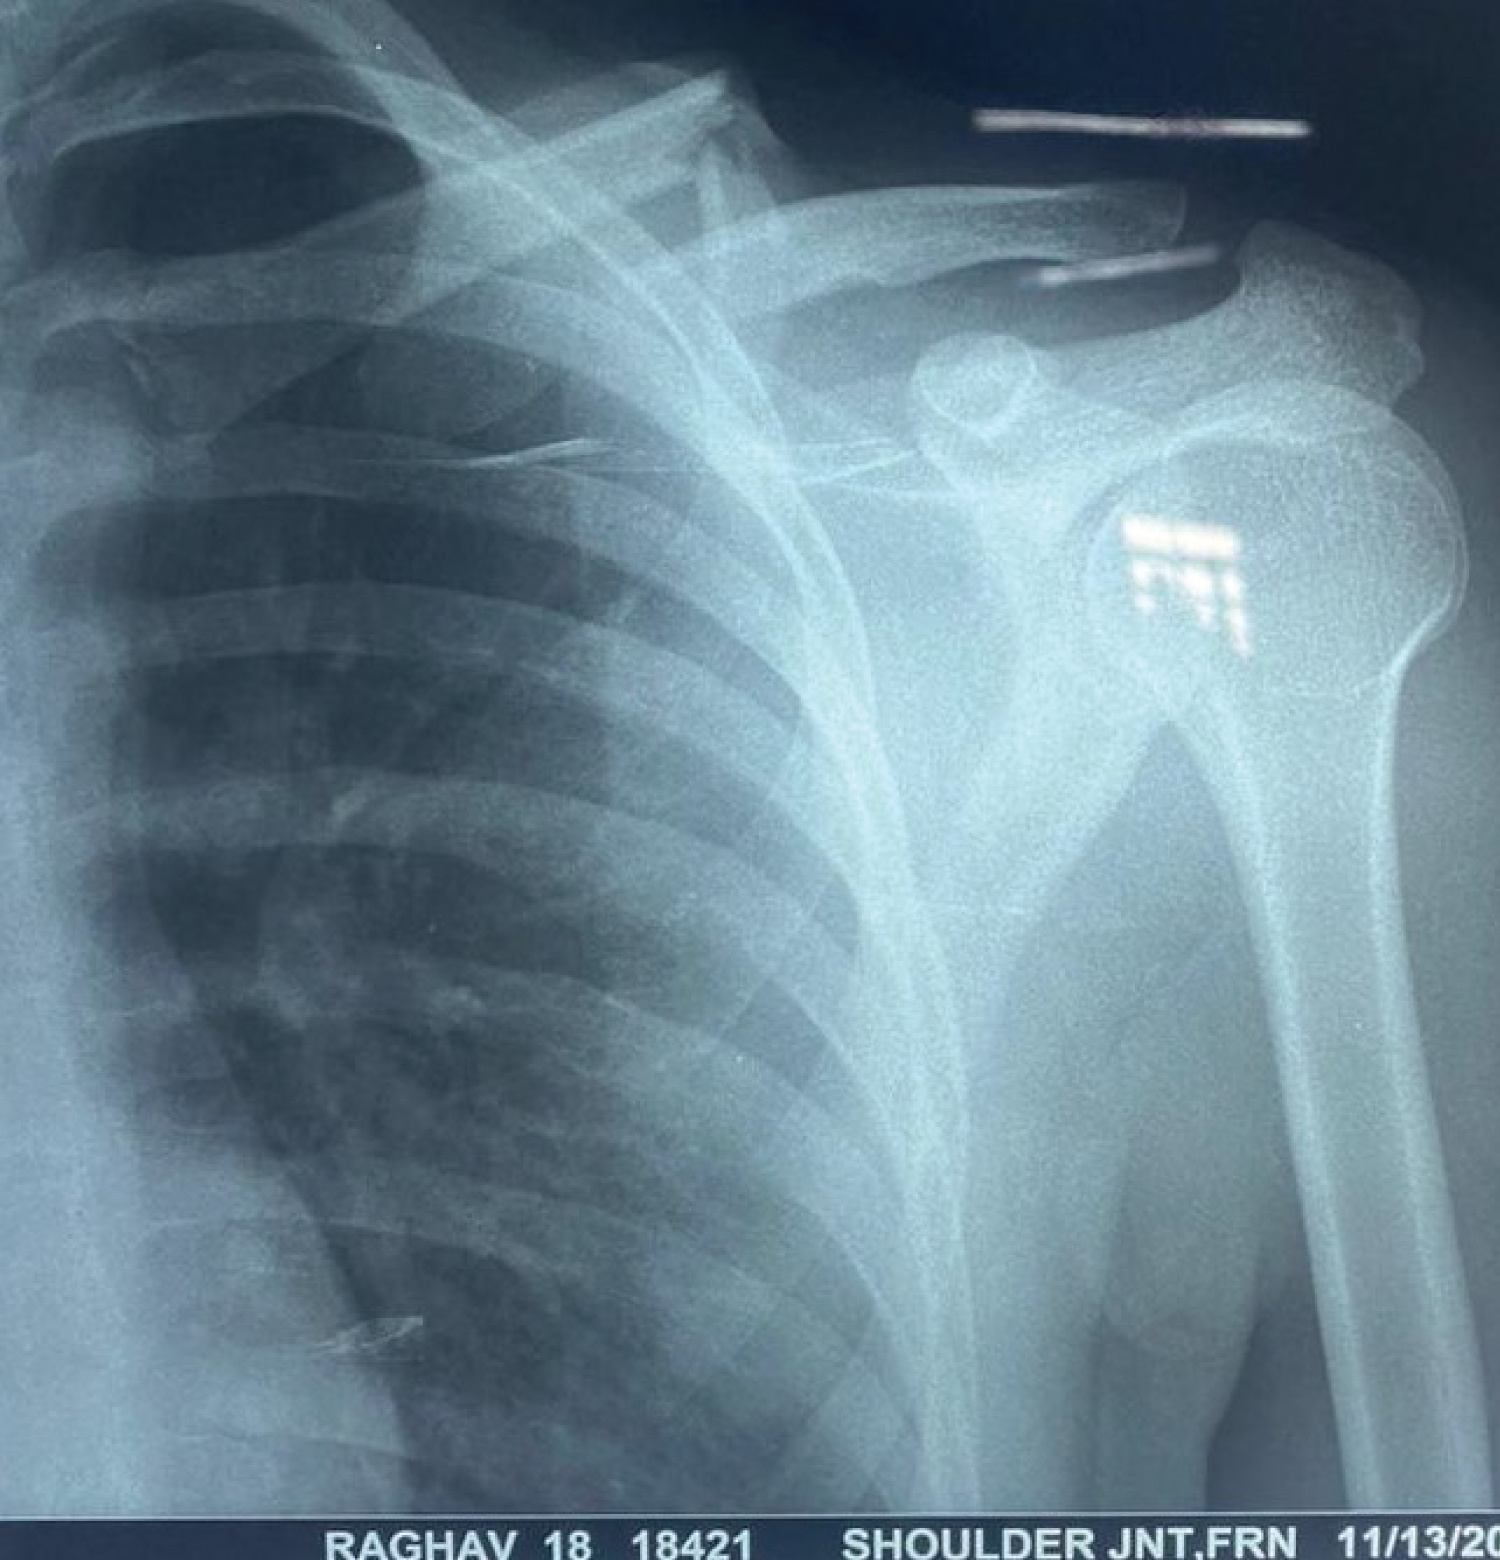

Anteroposterior radiographs can best assess a clavicle fracture, especially in the proximal portion of the clavicle (Figure 1). Computed tomography (CT) imaging can be utilized for evaluation of intra-articular involvement of the medial and lateral ends of the bone and preoperative and detailed evaluation of the injury (Figure 2).

Figure 1: Anteroposterior radiograph of the clavicle showing segmental fracture of the clavicle on the left side. View Figure 1